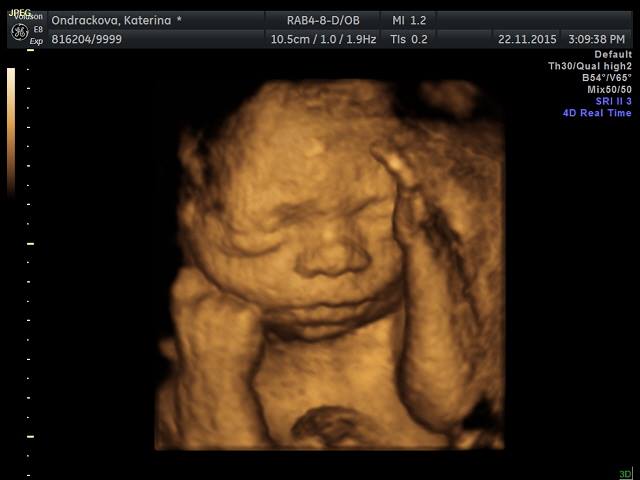

Ja byla na 3D vcera a supr :-) Mame video a 18 fotek. Ze zacatku to vypadalo tragicky, mimi oblicejem zaboreny v placente ale pak ho sestricka nasla z jinyho uhlu. Platila sem neco kolem 1300. Ted je nejlepsi doba na to jit kvuli velikosti mimi a mnozstvi plodovky. Tak sup holky ;-)

Ted su konecne na pc, tak prikladam vcerejsi ulovky

Jeeee, Kačenko, tak to nema chybu, ten jazyk je super :-D moc pekne vam to vyšlo. Mimiško je krasny. Až mě to 3D trochu mrzi ze nejdeme. Ja se zrovna chystam na tu cukrovku.

Gaga-Kacenka: Jůůů, krááásný, ten jazyk to se fakt povedlo ;)))!!! Tak už se taky moc těším, snad bude malá spolupracovat a nebude se schovávat ;).

.Kacko.. tak to fakt nema chybu ten jazyk :) hezke... a prvni fotka roztomila..